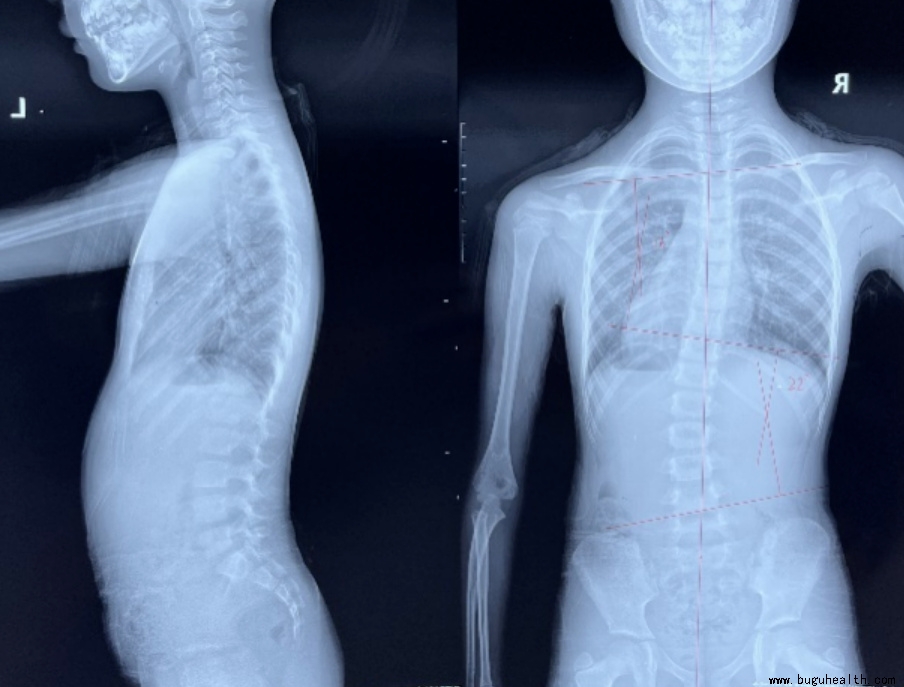

脊柱侧弯的诊断标准是cobb角大于10度,所以当家长自己在家用六部筛查法怀疑自己孩子有可能有脊柱侧弯的时候,你就应该带孩子到医院找专业的医生进行进一步确诊,当我们通过影像学确诊为脊柱侧弯的时候,我们会根据孩子的年龄、侧弯度数来建议目前孩子适合的矫正方法,目前对于脊柱侧弯的矫正大致分为三种:一是康复训练即矫形体操;二是体操加矫形支具;三是手术。

脊柱侧弯(又称脊柱侧凸),是以脊柱的某一段持久地偏离身体中线,使脊柱向侧方凸出弧形或“S”形为主要表现的疾病。

严重的畸形不仅影响孩子外观,例如高低肩、含胸驼背、剃刀背,这些都会导致自卑、抑郁、缺乏自信等心里情绪问题,还会给孩子造成心肺功能降低,例如出现呼吸困难或者呼吸急促等问题,也会出现神经压迫,当侧弯到达一定的程度时神经就会受到压迫,会出现麻木疼痛等相关神经症状,如果侧弯继续加大,在纵向力的冲击下可能会发生脊柱骨折,导致脊髓损伤可能瘫痪,甚至危及生命。